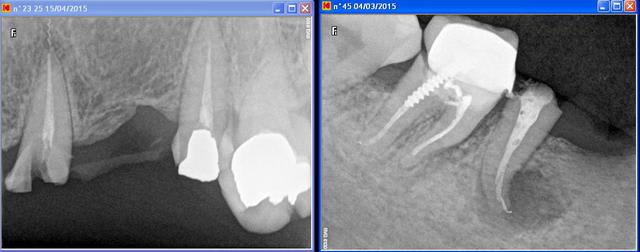

Le bridge de cette patiente se descelle (pas vraiment étonnant vu l'absence d'ancrage) et je lui propose donc d'en refaire un tout beau tout neuf.

Sauf que j'ai un bout de lentulo au bout de la 23 qui m'mbête un peu, je prévois de toute façon le retraitement de la dent puisque le bridge n'est plus étanche depuis un moment mais pensez-vous qu'il soit judicieux de faire enlever ce bris instrumental (rapport bénéfice/risque?).

Ps Pour la racine D de 46 j'ai fait retraitement et pose d'Ic + provisoire avec réserve il y a un mois mais ça suinte toujours par la fistule (+ avis demandé à la chir comme de toute façon je l'envoie pour 23)- Puis-je en espérer quelque chose? (c'est louche aussi sous 47)

Pour la 23 faut enlever le lentulo

Pour la 46...chirurgie pour enlever la lésion, et probablement la racine...

Pour le problème spécifique du lentulo, j'aurais tendance à reprendre tranquillement mon endo, reconstruire dessus as usual, et résection si nécessaire par la suite. Aussi bien, dans 30 ans, il est toujours là.